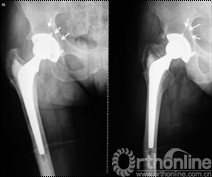

女,50岁,因髋关节发育不良继发骨关节炎行混合性固定(非骨水泥髋臼,骨水泥柄)THA手术。术后6年4个月发现腹股沟部渐增大、无痛性包块;体查:关节活动正常,腹股沟处可触及一10mm×10mm大小、质中等、移动度差、无触痛包块。超声检查提示右髂窝包块,呈强弱不等回声,大小约12cm×10cm,边界清楚。Harris评分88分。X线片示髋臼顶部DeLee和Charnley II区不规则低密度透光区,无连续骨小梁(图5)。CT片示髋臼假体上方DeLee和Charnley II区骨溶解区,DeLee和Charnley I、III区髋臼假体骨长入固定(图6)。WBC6.7×109/L,中性64%,ESR 28mm/h,CRP 8.34mg/L。聚乙烯线性磨损率为0.17mm/年,容积磨损率为543.42mm3/年,骨溶解区面积为412.52mm2。诊断:THA术后髋臼假体周围局灶性骨溶解(假体稳定)伴假性瘤样形成。

图5   翻修术前髋关节正侧位X线片示髋臼顶部DeLee和Charnley II区不规则低密度透光区(箭头所示),髋臼假体稳定固定

图6  CT片示髋臼假体上方DeLee和Charnley II区骨溶解, I、III区骨长入固定,髂窝内假性瘤样肉芽肿(箭头所示)

择期行双切口入路(髂腹股沟入路联合髋关节后外侧入路)右腹股沟炎性假瘤切除、骨溶解病灶清除、同种异体颗粒骨植骨、更换负重界面手术治疗。经髂腹股沟入路,见右髂窝内边界清楚,囊壁完整、质中等包块,切开囊壁,可见包块内黄色干酪样物(图7),清除干酪样物,完整切除包块囊壁,见囊壁基底位于髋臼内侧壁并与髋臼通过一直径约5mm骨缺损区相同。术后组织学可见异物吞噬反应(图8)切除髂窝炎性假瘤,经髂骨内板骨缺损区清除髋臼骨溶解病灶,同种异体颗粒骨打压植骨。髋关节后外侧入路更换高分子聚乙烯内衬为高交联聚乙烯内衬,更换钴铬钼股骨头为陶瓷头(图9)。术后2年随访,髋臼骨溶解区新生骨组织替代,髋臼假体无移位、假体稳定固定(图10),CT扫描显示骨溶解区骨长入良好,髋臼骨长入固定(图11)。Harris评分95分。超声复查无关节周围包块。

图9 髂腹股沟入路炎性假瘤切除、骨溶解病灶清除、同种异体颗粒骨植骨,髋关节后外侧入路更换高分子聚乙烯内衬为高交联聚乙烯内衬、更换股骨头术后

图10 术后2年随访,植骨替代吸收,髋臼骨溶解区新生骨组织替代,髋臼假体无移位、假体稳定固定

图11 术后2年随访,CT扫描显示髋臼骨溶解区新生骨组织替代,骨溶解区骨长入良好,髋臼骨长入固定